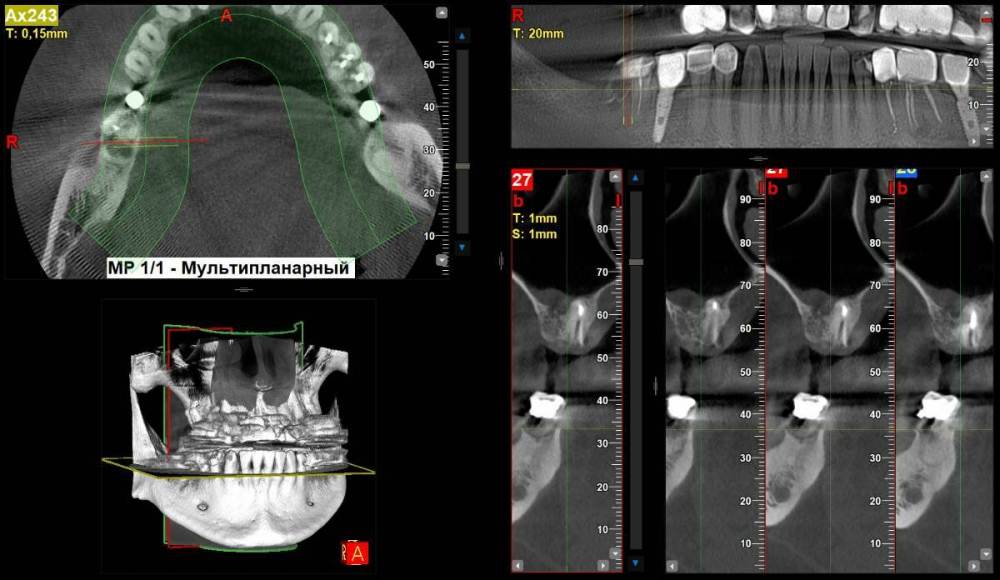

2. Зуб 47, один из корней сгнил, но неболит.  Есть вариант сделать гемисекцию и одеть коронку. Ваше мнение и прогноз? Почему то все хирурги усмехаюся когда я спрашиваю про этот метод.

2 учитывая ту картину, которую видно на панорамной реконструкции, зуб 4.7 нужно удалять

2. Зуб 47 лучше удалить. Гемисекция в данном случае не показана.

47_1.thumb.jpg.72d534cee08a7599a65a246afa26dd77.jpg

47_2.thumb.jpg.55b2ff233eb674b4d633d71b2182fcc6.jpg